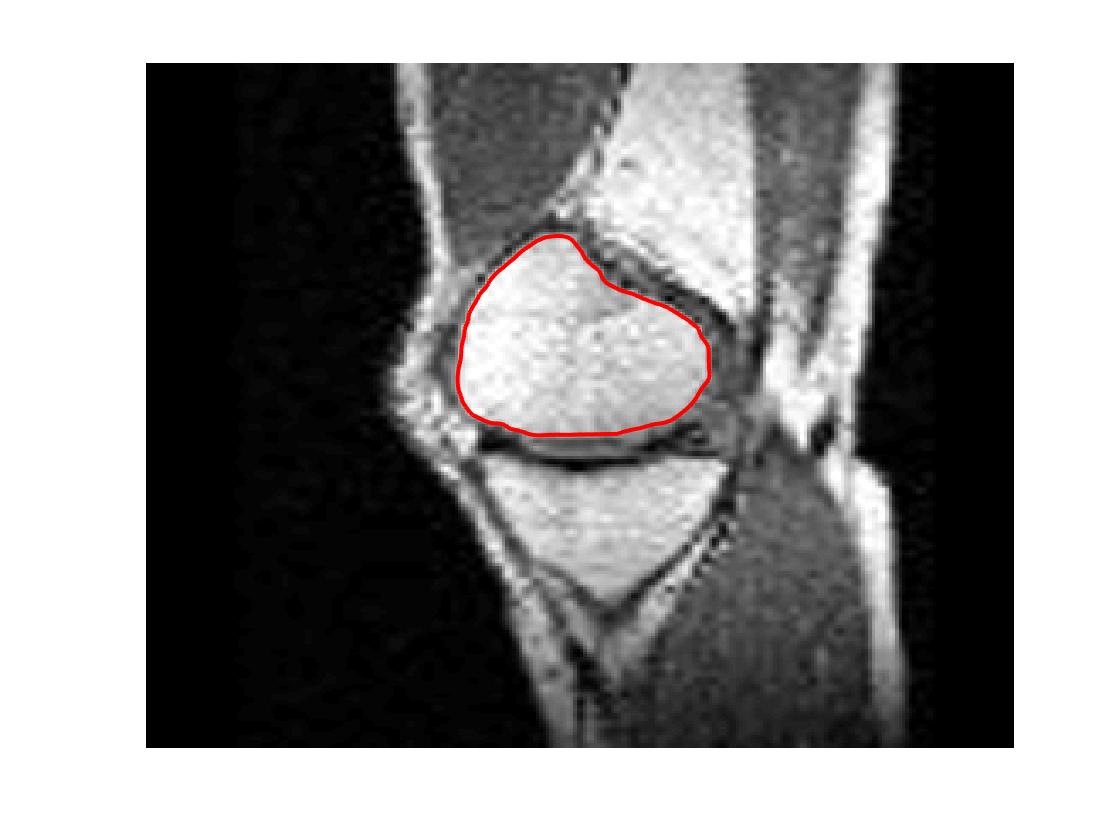

Four sets of test results are shown below. In Test 1 we compare models M1 – M6 to the proposed model M7 for two images which are hard to segment. The first is a CT scan from which we would like to segment the lower portion of the heart, the second is an MRI scan of a knee and we would like to segment the top of the Tibia. See Figure 9 for the test images and the marker sets used in the experiments. In Test 2 we will review the sensitivity of the proposed model to the main parameters. In Test 3 we will give several results achieved by the model using marker and anti-marker sets. In Test 4 we show the initialisation independence and marker independence of the Geodesic Model on real images.

Refer to captionRefer to captionRefer to captionRefer to caption

(i)                                 (ii)                                 (iii)                                 (iv)

Figure 9: Test 1 setting: (i) Image 1;  (ii) Image 1 with marker and anti-marker set shown in green and pink respectively;  (iii) Test Image 2; (iv) Image 2 with marker set shown.

Figure 11: Visual comparison of M1 – M7 results for Test Image 2. M1 segmented part of the object, M2 – M4 failed to segment the object, M5, M6 and M7 correctly segmented the object.